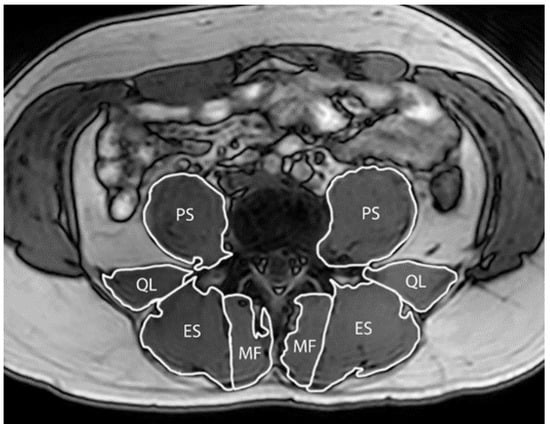

2.3.2. Paraspinal Muscle Size

| Multifidus Volume (cm3) | ||||||

| Baseline | 18.2 (4.0) | 0.102 | 18.0 (5.5) | 0.477 | 0.6 (−0.1, 1.4) | 0.096 |

| ∆ 3 months | 0.4 (−0.1, 1.0) | −0.2 (−0.7, 0.3) | ||||

| ∆ 6 months | 0.8 (0.3, 1.3) | 0.003 | 0.2 (−0.3, 0.7) | 0.463 | 0.6 (−0.1, 1.4) | 0.116 |

| Erector Spinae Volume (cm3) | ||||||

| Baseline | 45.9 (11.2) | 0.506 | 48.7 (15.3) | 0.884 | 0.5 (−1.2, 2.2) | 0.570 |

| ∆ 3 months | 0.4 (−0.8, 1.6) | −0.1 (−1.3, 1.1) | ||||

| ∆ 6 months | 0.1 (−1.1, 1.3) | 0.810 | 0.1 (−1.1, 1.4) | 0.822 | 0.0 (−1.7, 1.7) | 0.998 |

| Psoas Major Volume (cm3) | ||||||

| Baseline | 32.8 (9.7) | 0.697 | 32.5 (11.5) | 0.157 | 0.3 (−1.1, 1.7) | 0.677 |

| ∆ 3 months | −0.2 (−1.4, 0.9) | −0.5 (−1.3, 0.2) | ||||

| ∆ 6 months | 0.2 (−0.9, 1.4) | 0.686 | 0.0 (−0.7, 0.8) | 0.967 | 0.2 (−1.2, 1.7) | 0.761 |

| Quadratus Lumborum Volume (cm3) | ||||||

| Baseline | 11.2 (3.4) | 0.428 | 11.6 (4.4) | 0.697 | 0.0 (−0.8, 0.9) | 0.933 |

| ∆ 3 months | 0.2 (−0.3, 0.6) | 0.1 (−0.6, 0.9) | ||||

| ∆ 6 months | 0.1 (−0.4, 0.5) | 0.813 | 0.3 (−0.5, 1.0) | 0.472 | −0.2 (−1.0, 0.6) | 0.614 |